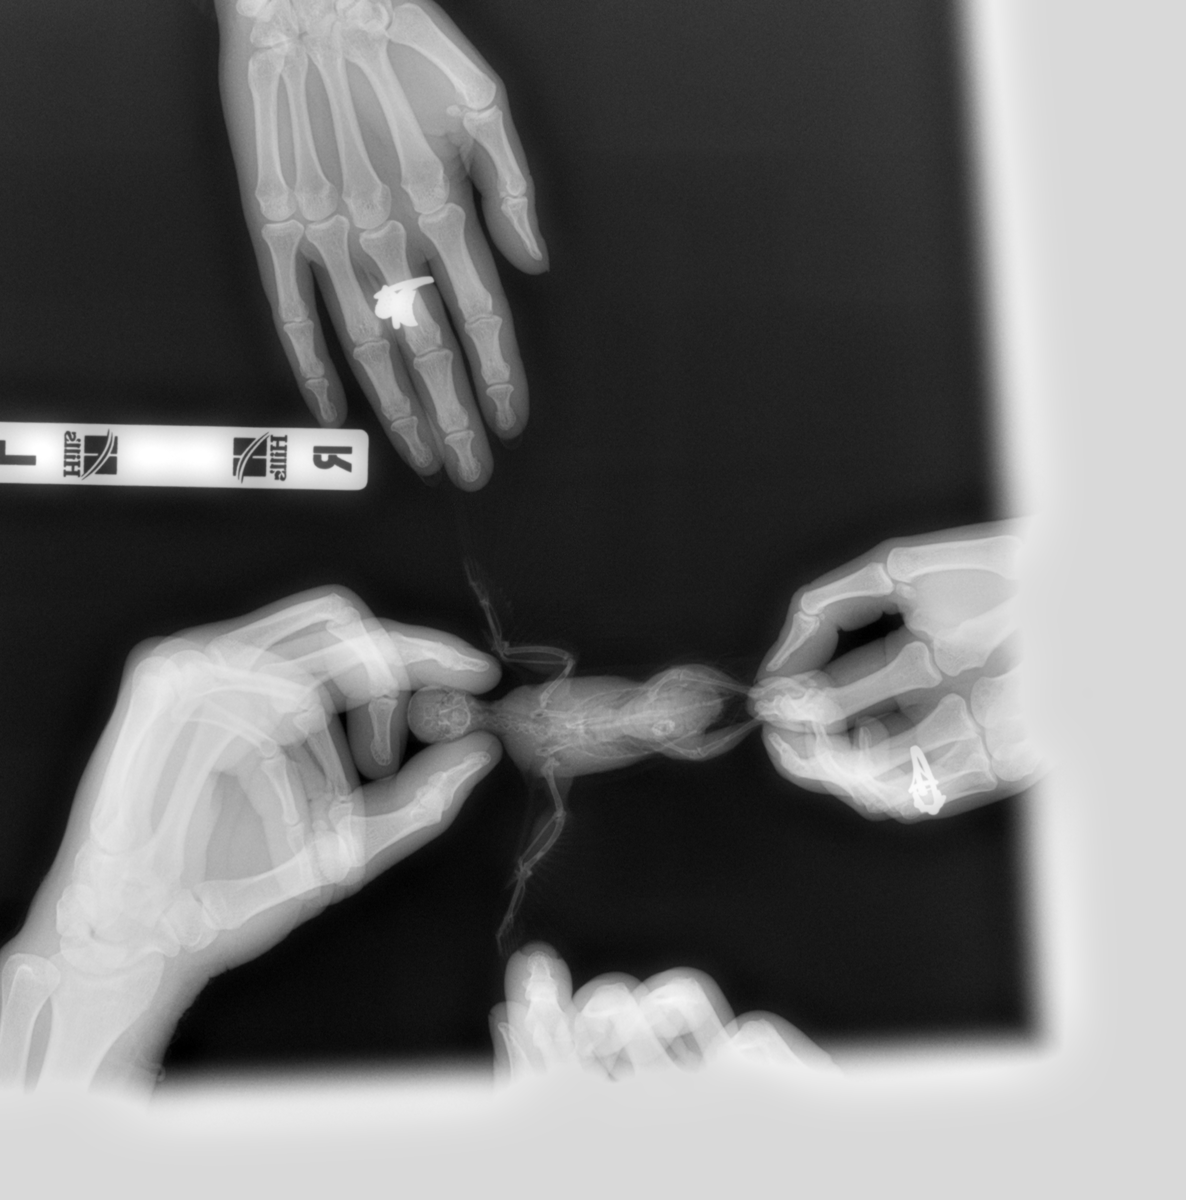

Venni Опубликовано 6 апреля, 2019 Автор #189 Опубликовано 6 апреля, 2019 (изменено) @KamaRo сделали мы рентген, делали у того же доктора, что и 2 недели назад, сравнивали прошлый снимок и новый, изменений нет, единственное уменьшились гастролиты в мускульном желудке, в диагнозе так и написал - На рентгене ( какое-то непонятное мне слово) мускульного желудка визуализируются гастролиты. Никаких яиц он не видит. Выкладываю фото 1 рентгена и последнего. Боковой мы не делали, так как не хотела птицу второй раз облучать. Вот эта белая точка с правой стороны, он мне объяснил, что это гастролиты в мускульном желудке. Изменено 6 апреля, 2019 пользователем Venni

Zosia Опубликовано 7 апреля, 2019 #193 Опубликовано 7 апреля, 2019 Да,можно. У птицы неравномерная плотность трубчатых костей. Гастролиты у попугаев редки (все должно арстворяться кислотами желудков),и как правило выглядят вот так https://public.fotki.com/Shemlik/7a930/20170610-104549-jpg.html#media снимок позитивный четко видны мелкие конкременты На вашем я не могу их увидеть,но возможно вы их видите(разрешение у вас позволяет это сделать)